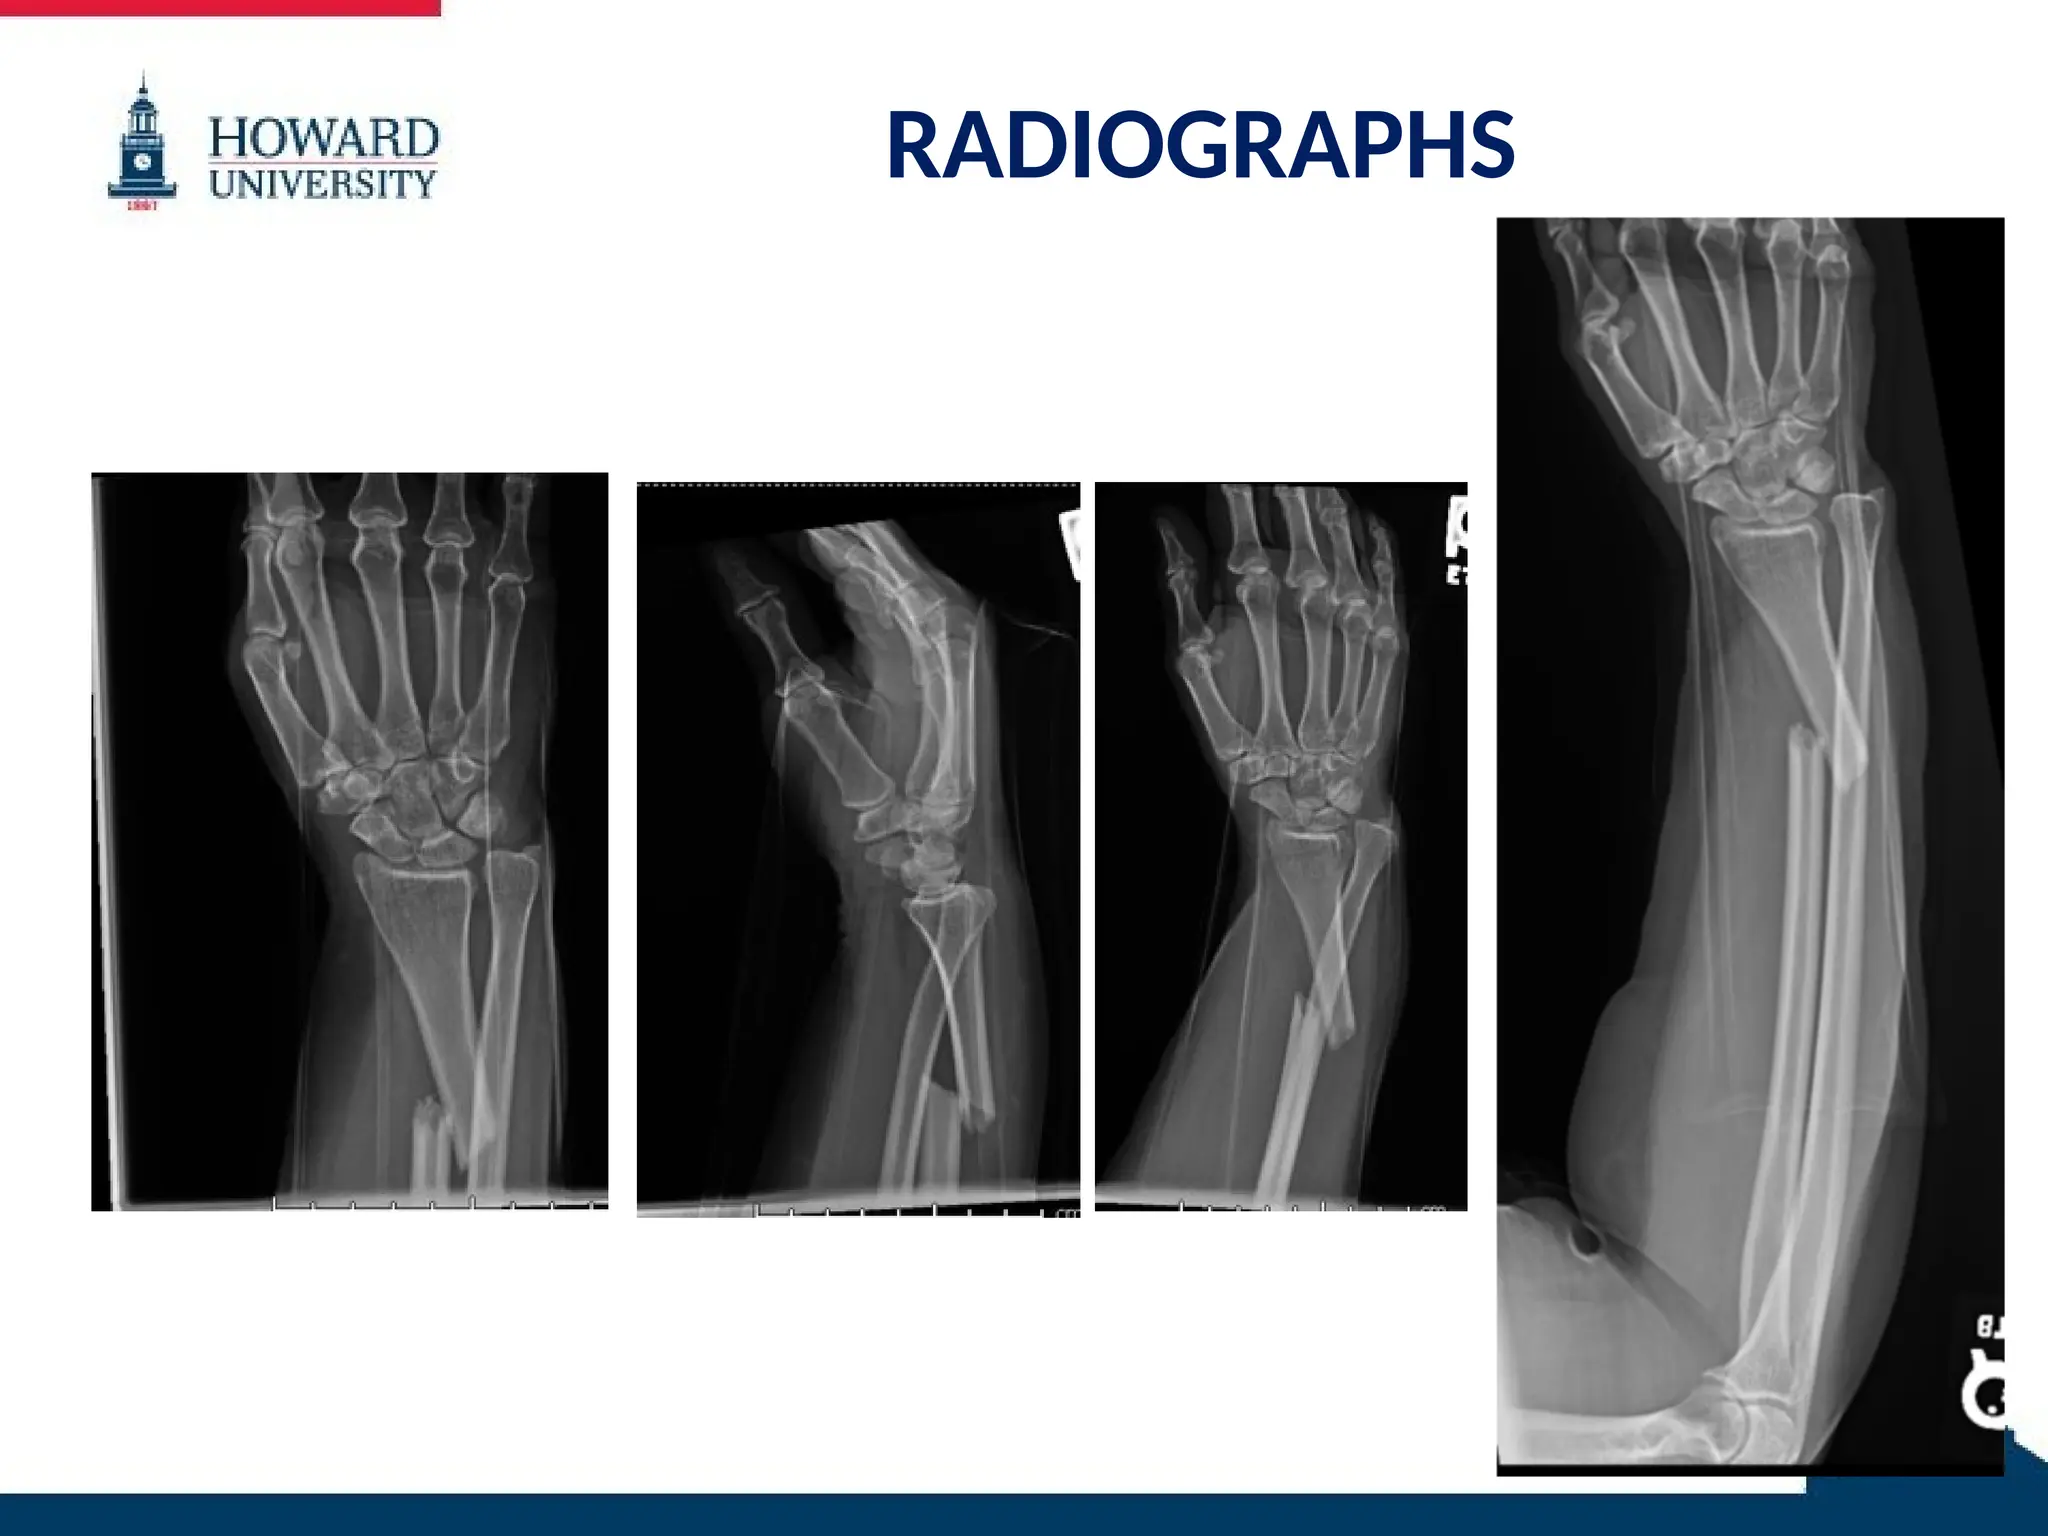

RADIOGRAPHS

59 YO female with right distal 1/3 radial

diaphyseal fracture with associated DRUJ

dislocation

– Walsh type II

– Rettig and Raskin type I

– AO/OTA 22A2.3